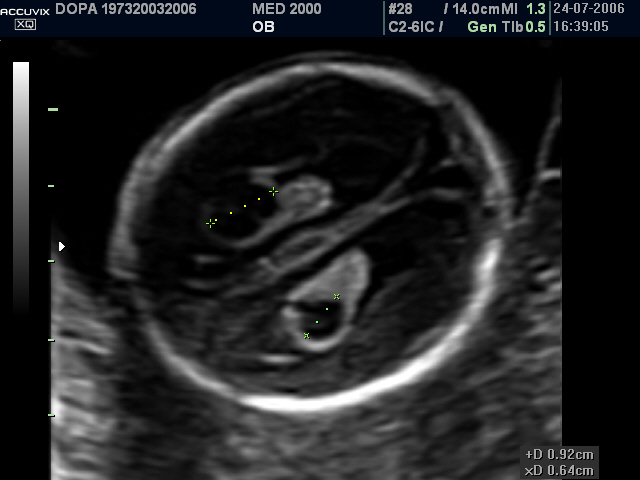

Ecograficamente si presentano come aree cistiche rotondeggianti o ovalari, uniloculari o settate, di diametro variabile da 3 a 9 mm., singole o multiple, monolaterali o bilaterali, localizzate più frequentemente nei plessi corioidei dei ventricoli cerebrali laterali, meno frequentemente nel III e IV ventricolo.